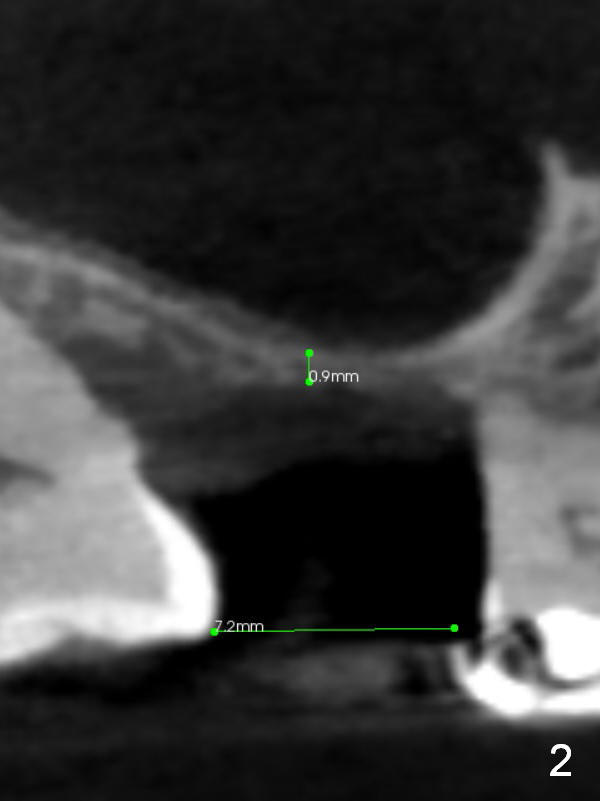

A 78-year-old man needs implant restoration at #2 in spite of limited bone height, because of severe ridge atrophy at #18 and 19. Sagittal (Fig.1-3) and coronal (Fig.4-6) sections show bone height less than 1 mm. If there is plenty of the keratinized tissue at #2, use a 4 mm tissue punch for access, followed by sinus lifter. Use fine and coarse allograft for sinus lift.